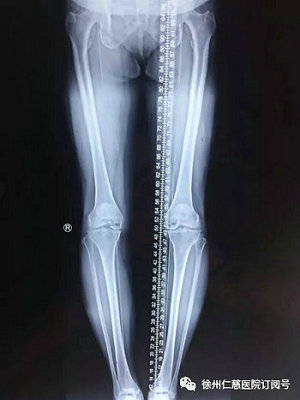

当时,王老师找到保膝门诊的邱东新医生,邱医生仔细查看了王老师的膝关节情况,结合拍摄的片子,确诊王老师患的是左膝骨性关节炎,左膝关节内翻畸形,因为长时间疼痛未作有效治疗,左下肢已经比右腿短了约0.5厘米。同时,老人还患有高血压和糖尿病。